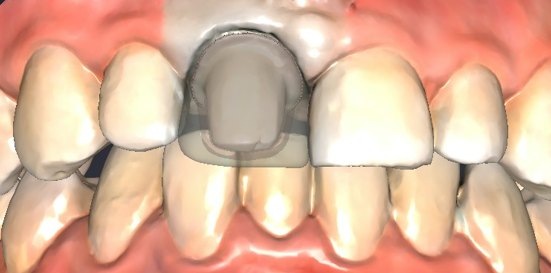

No Temporary Crowns. No Messy Putty.

Using our Intraoral Digital Scanner and In-House Milling, we design and create your high-strength ceramic restoration while you wait.

Digital 3D Scan (No gagging)

Precision Milling (Same-day final)

Bioactive Bonding (Heals the tooth))

Intraoral Digital Scanner

Our Intraoral Digital Scanner replaces the dreaded “messy putty” with a fast, high-definition 3D camera. This technology ensures a gag-free experience while capturing an incredibly accurate map of your teeth in seconds.